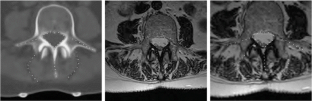

In this chapter we are concerned with variational methods in image analysis. Special attention is paid on free discontinuity approaches of Mumford Shah type and their application in segmentation, matching and motion analysis. We study combined approaches, where one simultaneously relaxes a functional with respect to multiple unknowns. Examples are the simultaneous extraction of edges in two different images for joint image segmentation and image registration or the joint estimation of motion, moving object, and object intensity map. In these approaches the identification of one of the unknowns improves the capability to extract the other as well. Hence, combined methods turn out to be very powerful approaches. Indeed, fundamental tasks in image processing are highly interdependent: Registration of image morphology significantly benefits from previous denoising and structure segmentation. On the other hand, combined information of different image modalities makes shape segmentation significantly more robust. Furthermore, robustness in motion extraction of shapes can be significantly enhanced via a coupling with the detection of edge surfaces in space time and a corresponding feature sensitive space time smoothing. Furthermore, one of the key tools throughout most of the methods to be presented is nonlinear elasticity based on hyperelastic and polyconvex energy functionals. Based on first principles from continuum mechanics this allows a flexible description of shape correspondences and in many cases enables to establish existence results and one-to-one mapping properties. Numerical experiments underline the robustness of the presented methods and show applications on medical images and biological experimental data. This chapter is based on a couple of recent articles (Bar et al., A variational framework for simultaneous motion estimation and restoration of motion-blurred video, 2007; Litke et al., An image processing approach to surface matching, 2005; Droske et al., Comput. Vis. Sci. Online First, 2008; Droske and Rumpf, SIAM Appl Math 64(2):668–687, 2004; Droske and Rumpf, IEEE Trans Pattern Anal Mach Intell 29(12):2181–2194, 2007; Rumpf and Wirth, SIAM J Imag Sci, 2008) published by the author together with Leah Bar, Benjamin Berkels, Marc Droske, Nathan Litke, Wolfgang Ring, Guillermo Sapiro, Peter Schröder, and Benedikt Wirth.

The author is grateful to Werner Bautz, radiology department at the university hospital Erlangen, Germany, for providing CT data of kidneys, as well as to Heiko Schlarb from Adidas, Herzogenaurach, Germany, for providing 3D scans of feet, and to Bruno Wirth, urology department at the Hospital zum Hl. Geist, Kempen, Germany, for providing thorax CT scans. Furthermore, the author thanks Stan Osher for pointing to the issue of elastic shape averaging and Marc Droske for discussion about the phase field approach. Finally, he acknowledges Helene Horn for her help in the careful preparation of the manuscript.